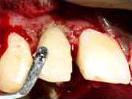

Labial Soft Tissue

Reflected

Tooth with Fracture Extending Sub-Gingivally

Palatal Soft Tissue